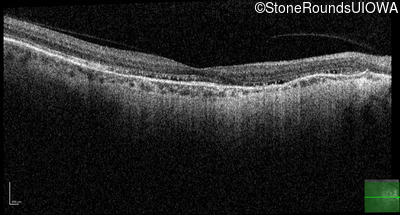

Age at visit: 56 years